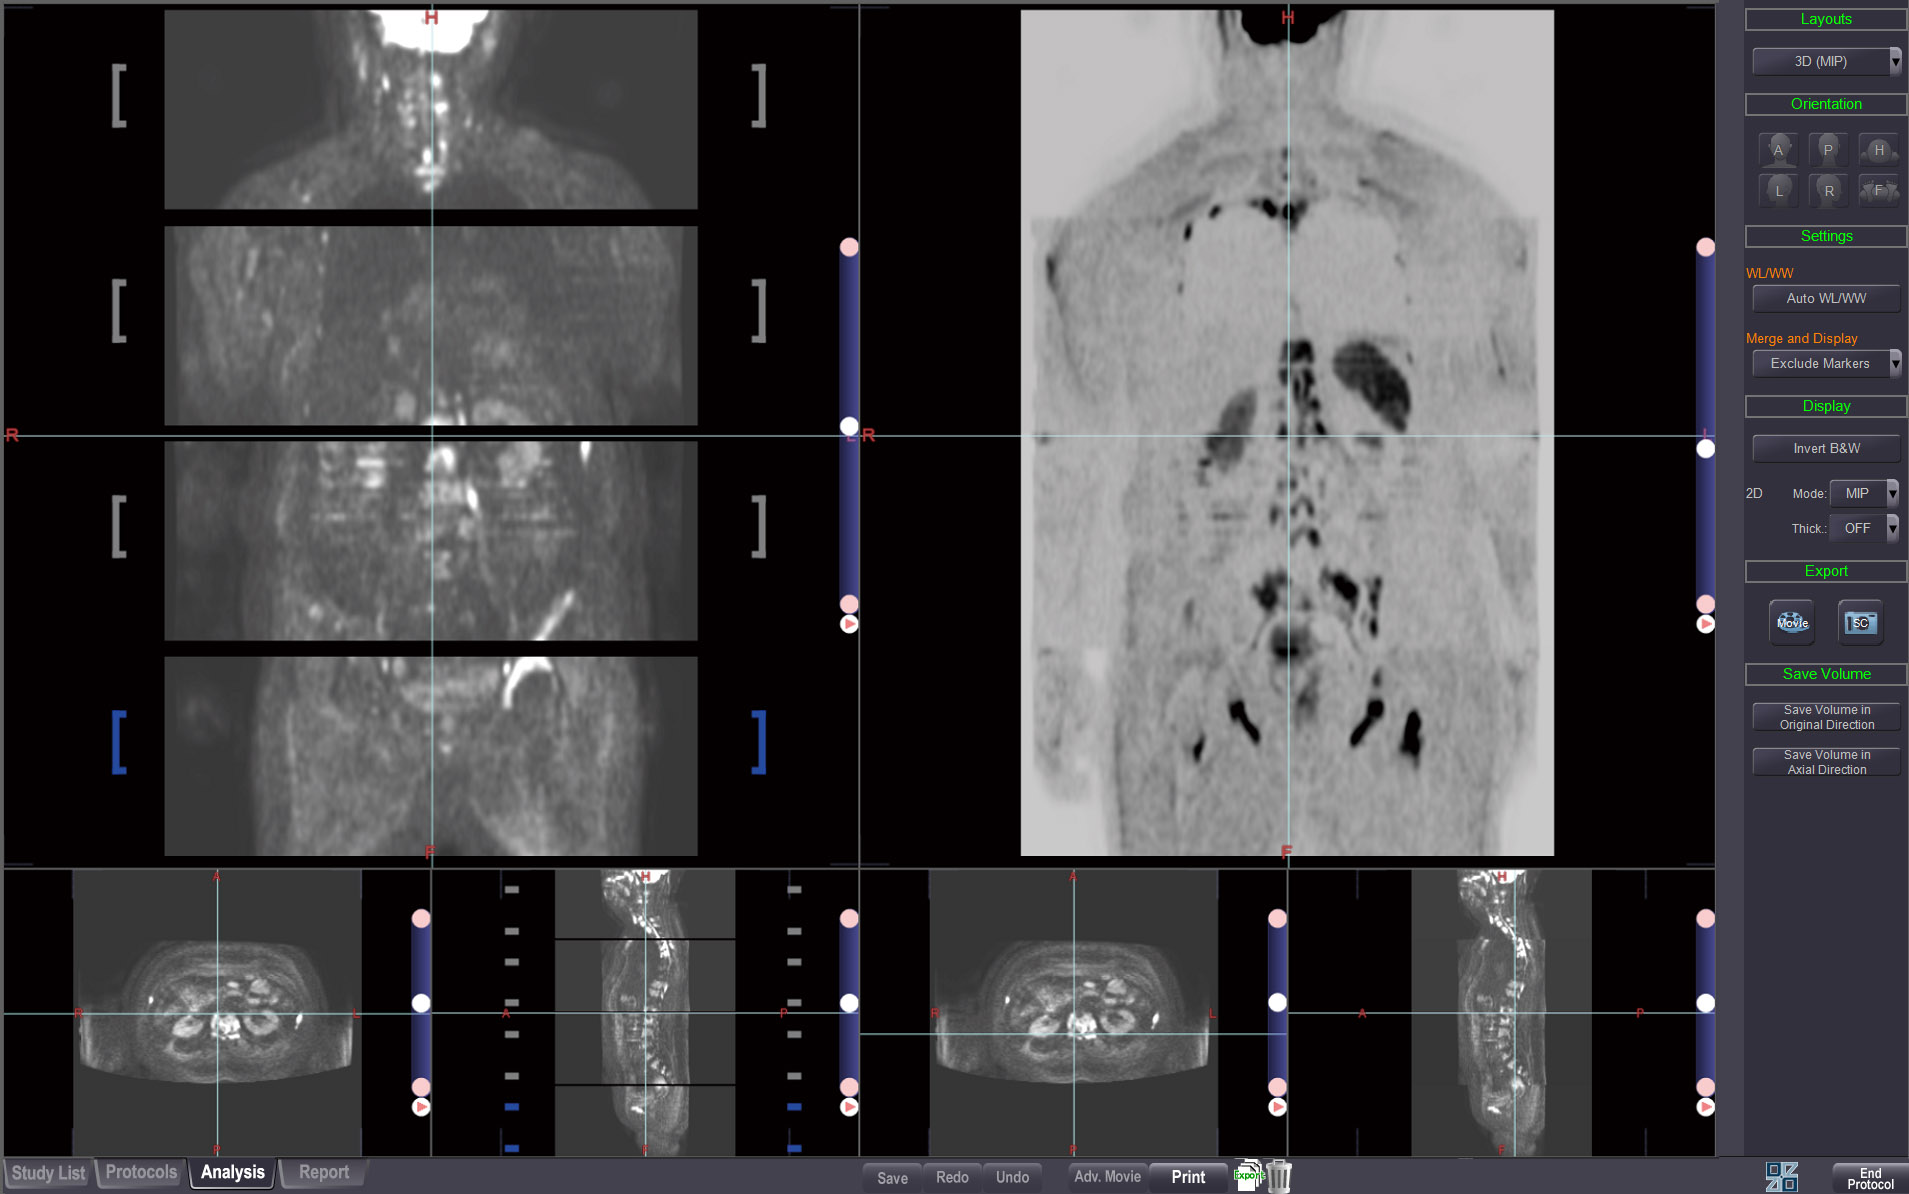

MR COMBINATION

Stitch multiple MR series and observe, combine and save into one series.